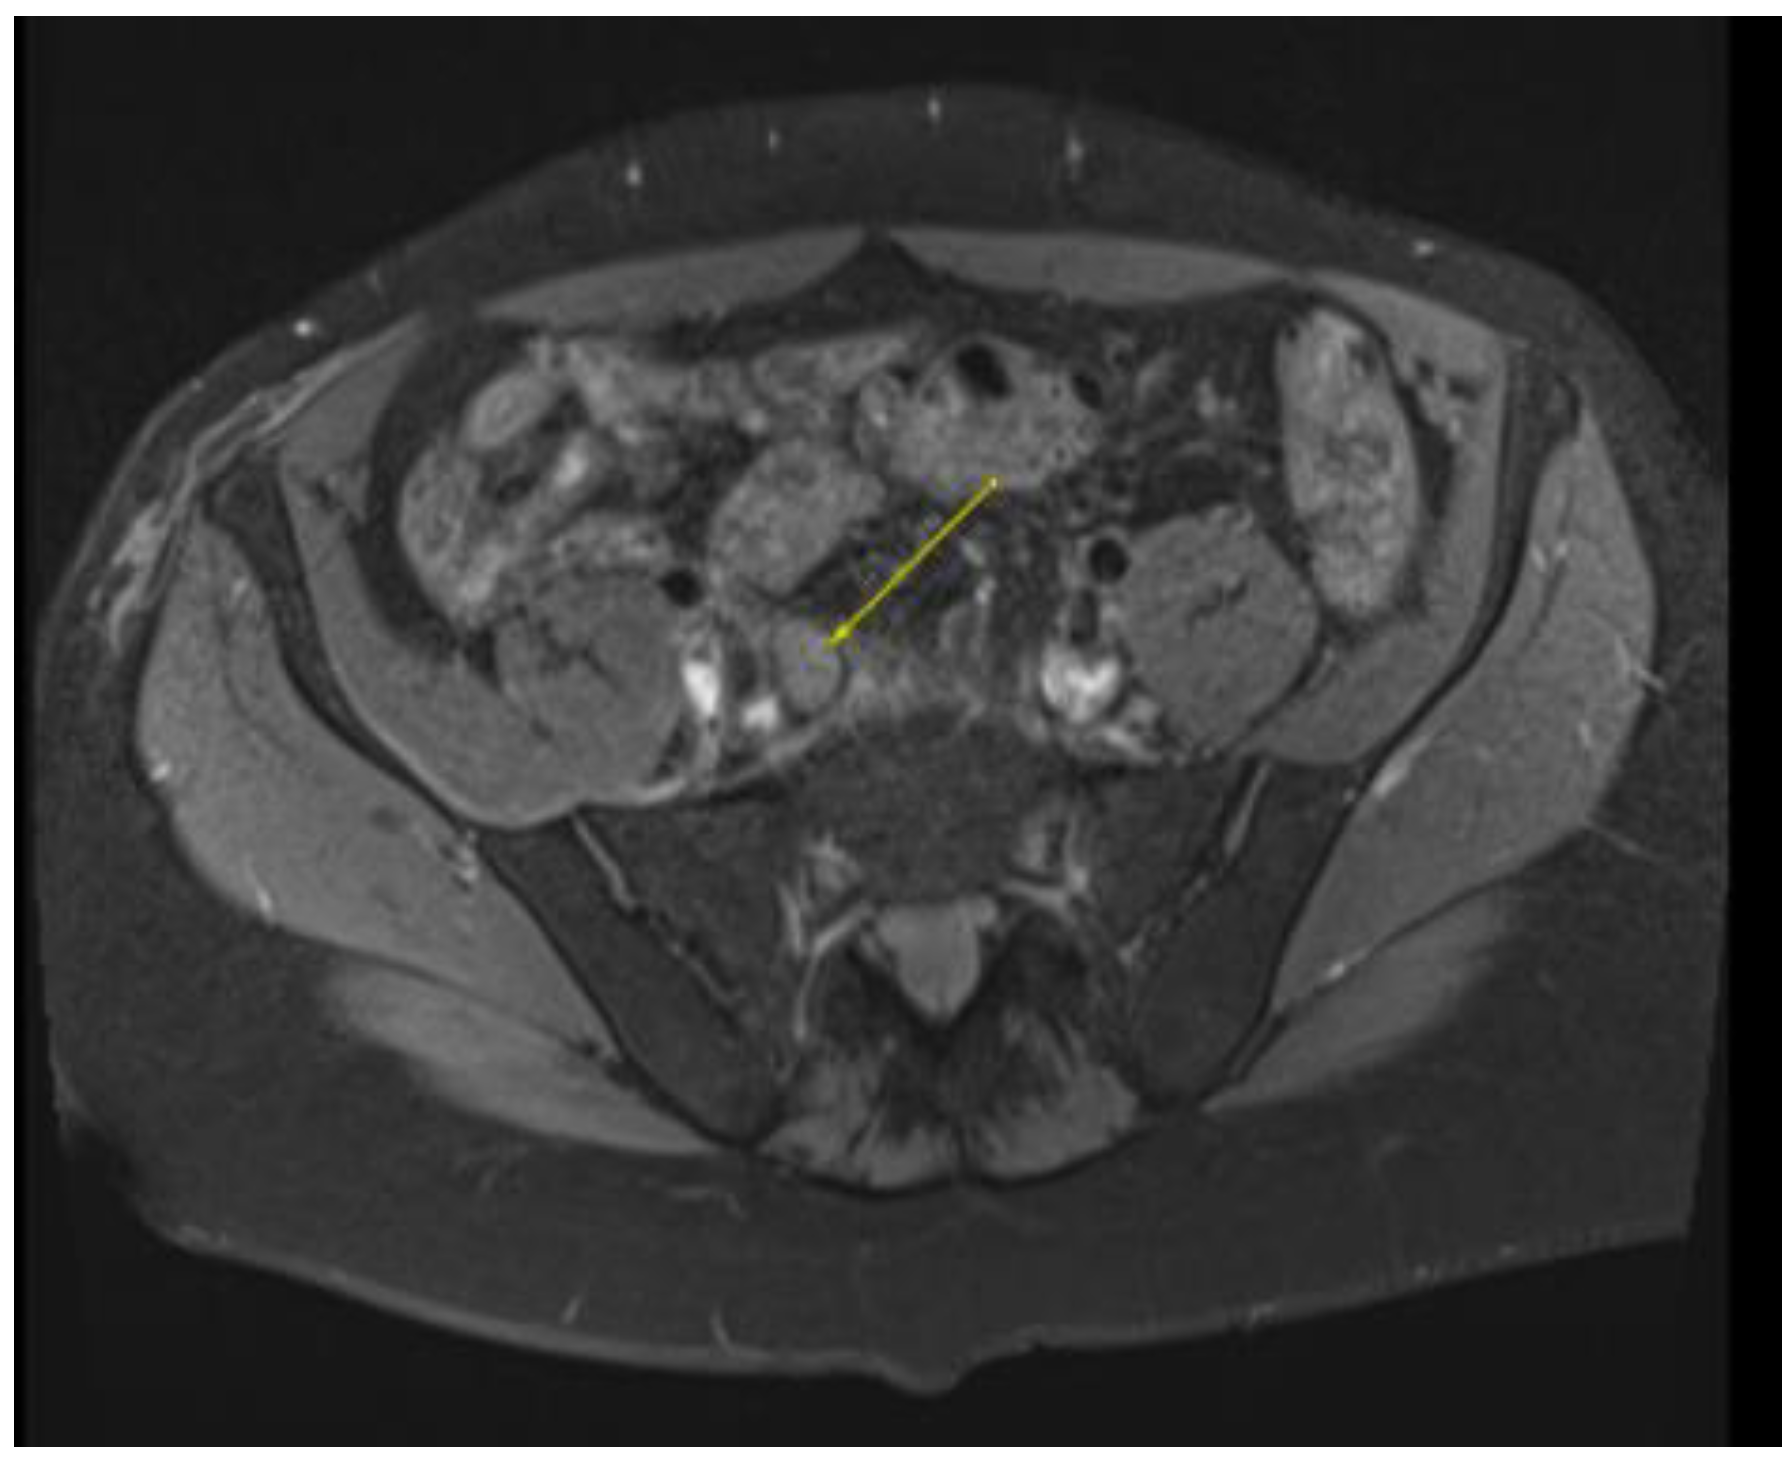

Figure 3.

MRI in the axial view T1 TSE FS PRE showing hyperintense linear non-enhancing structure consistent with ultrasound finding of thrombosed dorsal penile veins.